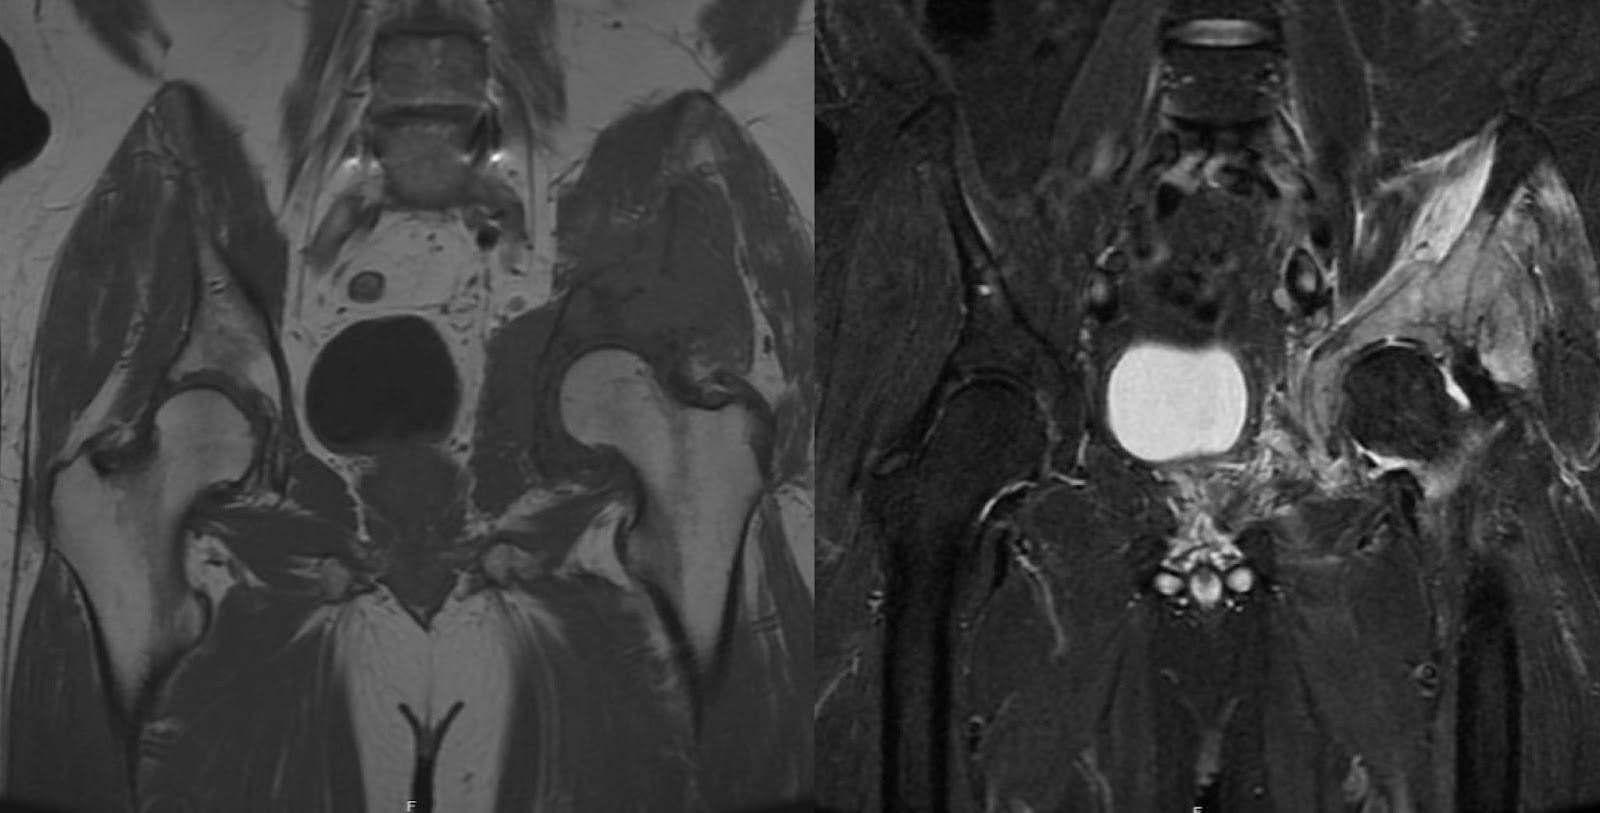

O LDGCB é o subtipo mais prevalente de linfoma não-Hodgkin, constituindo aproximadamente 30 a 40% de todos os casos. 1 O diagnóstico geralmente ocorre entre a quinta e a sexta décadas de vida. Sua etiologia é multifatorial e pode envolver predisposições genéticas, desregulação imunológica, bem como exposições virais, ambientais e ocupacionais. 2,3 É marcada pela proliferação de células linfopoiéticas, muitas vezes originadas no interior do osso, e tem o potencial de causar destruição localizada da arquitetura óssea, predispondo o indivíduo a fraturas patológicas. 4 Clinicamente, o LDGCB pode apresentar dor esquelética secundária à destruição e desestabilização óssea. Essa dor pode irradiar, principalmente quando há envolvimento de componentes localizados de tecidos moles, como nervos, músculos ou vasos, dependendo da localização da lesão. Sintomas sistêmicos como febre, sudorese noturna e perda de peso também podem fazer parte da constelação de sintomas. 2,4,5 A imagem geralmente revela destruição óssea radiolúcida com envolvimento de tecidos moles, evidente na radiografia simples. A ressonância nuclear magnética (RNM) geralmente mostra hipointensidade relativa nas sequências T1 no canal medular, indicando substituição da medula óssea. Além disso, as sequências T2 geralmente exibem hiperintensidade tanto na extensão intramedular quanto na extramedular. 6 Aproximadamente quatro anos antes da cirurgia de estabilização pélvica, a RM da paciente revelou lesão hipointensa em T1 e hiperintensa em T2 no acetábulo esquerdo e osso inominado, compatível com processo patológico nessas áreas (Figura 3). As massas de tecidos moles proeminentes frequentemente observadas na apresentação para LDGCB podem progredir sem intervenção sistêmica. As modalidades de tratamento padrão para LDGCB envolvem quimioterapia e radioterapia localizada. 7 O LDGCB tem um prognóstico moderado a favorável, com taxas de sobrevida em 5 anos variando de 60 a 70% após a terapia de primeira linha. 1

Figura 3. Ressonância magnética pré-operatória, realizada aproximadamente quatro anos antes da cirurgia de estabilização pélvica. A RM mostrou lesão hipointensa em T1 e hiperintensa em T2 no acetábulo esquerdo e osso inominado, sugestiva de processo patológico.